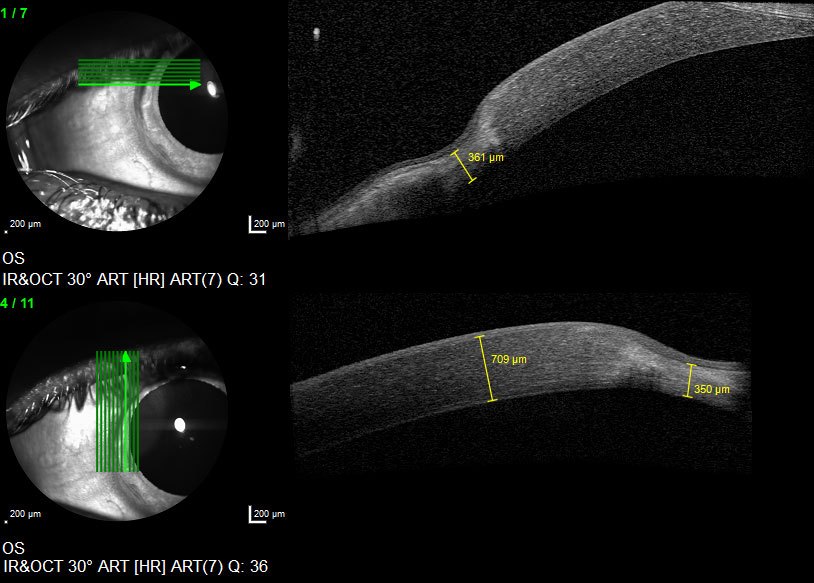

This OCT image shows a thinning of the cornea at the periphery (the edges) of the cornea)